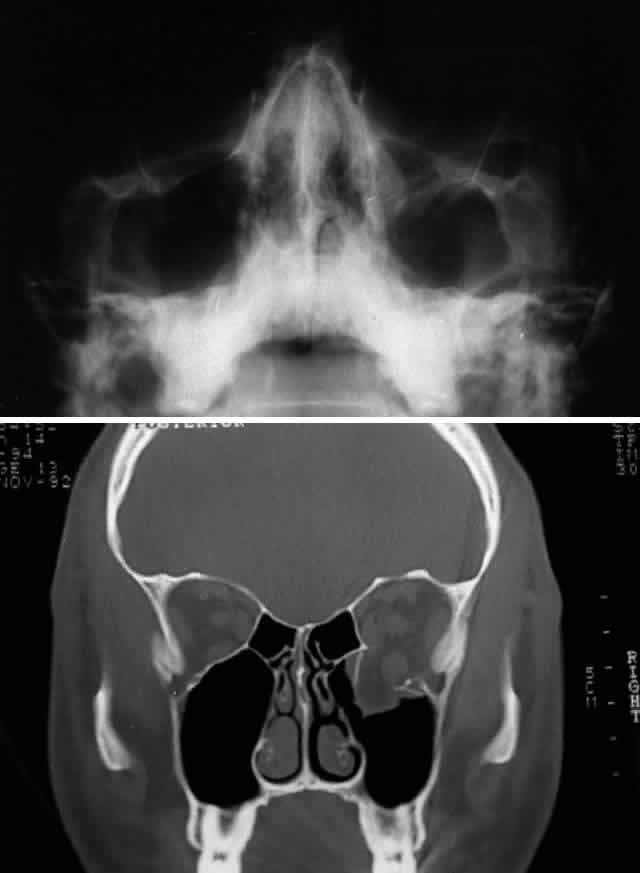

After the history and physical examination, consideration is given to further assessment of the orbital injury with radiologic imaging. The indications for radiologic imaging area are based on the physician's assessment of the injury and include gross orbital and facial deformity, limitation of ocular motility, and associated neurologic injuries. CT is the imaging modality of choice in the assessment of orbital/craniofacial fractures because it provides excellent detail of the bony injury as well as the orbital soft tissues in most cases (Fig. 4). Ideally, both axial and direct coronal views are preferred. Coronal views are necessary for adequate imaging of the orbital floor and orbital roof. With direct views, 3-mm views (cuts) are usually adequate. In cases in which the patients cannot be positioned for direct coronal imaging, coronal reconstructions can be performed, provided that finer (1.5-mm) axial cuts are used. Reconstructed coronal images lack the resolution of direct coronal images, but they are usually adequate when direct coronal imaging cannot be obtained. Spiral CT, which allows rapid imaging and multiplanar formatting, will likely become useful in the assessment of orbital trauma as this newer technology becomes increasingly available.

Before CT scanning was readily available, facial x-ray series were used in the radiologic assessment of orbital fractures. Typical views included Caldwell's (anteroposterior) view, Waters' view, lateral view, and submental vertex view (particularly good for viewing the zygomatic arches). Waters' view, which is obtained with the chin slightly elevated, is considered the most useful x-ray view for imaging the orbital floor, inferior rim, and maxillary sinus. Because CT scans are superior to x-rays in terms of sensitivity and reliability, in most situations today plain orbital/facial x-rays are obtained only when a CT scan is unavailable or when only very minimal injury is suspected. Magnetic resonance imaging (MRI), although able to image orbital soft tissue exquisitely well with a small surface coil, is generally of limited usefulness in the initial assessment of orbital/craniofacial injuries because of its limited ability to image bone. It is contraindicated in cases of suspected retained ferromagnetic foreign bodies. MRI may have a secondary role in the management of orbital trauma in cases where CT scanning suggests the presence of soft tissue injury, such as intramuscular hemorrhage or sub-dural optic nerve sheath hemorrhage. In such cases, the better soft tissue resolution potentially available with MRI may allow more specific diagnostic interpretation.2

Methods of stabilization include interosseous wiring and miniplate fixation. Interosseous wiring is generally sufficient for repair of isolated orbital fractures resulting from low-energy injuries. Higher energy injuries, which result in multiple orbital rim fractures and comminution, benefit from rigid miniplate fixation to maintain a stable three-dimensional reconstruction and improve osteosynthesis (Figs. 8, 9, and 10). Miniplate fixation allows bridging of areas of extensive comminution. Miniplates come in various sizes (i.e., plate thickness [“profile”] and screw size) and shape. Miniplates generally have a profile of at least 1 mm and utilize screws equal to or greater than 1.5 mm, whereas microplates have profiles on the order of 0.5 mm and screw sizes of approximately 1 mm. Plates and screws of intermediate size are also available, and these appear to be ideal for orbital reconstruction. Most miniplates (and screws) are composed of corrosion-resistant metals, such as titanium or vitallium (an alloy of cobalt, chromium, and molybdenum). Because these metals are nonmagnetic, postoperative MRI is not contraindicated after reconstruction with these materials. These materials do produce some artifact on CT scan; however, this artifact is less than that noted with stainless steel, with titanium having the least artifact.

MEDIAL ORBITAL RIM (NASOETHMOID-ORBITAL REGION). The bones of the medial orbital rim represent the lateral aspect of the nasoethmoid complex, and fractures of the medial orbital rim are most typically the component of a more generalized nasoethmoid orbital injury. Nasoethmoid orbital fractures may be isolated or associated with other more extensive craniofacial fractures (e.g., Le Fort II and III). Successful management of nasoethmoid orbital injury requires consideration of both the bony and soft tissue injury.38,39,45–47 The most important soft tissue structure in the nasoethmoid-orbital region is the medial canthal tendon. The medial canthal tendon has medial and posterior insertions to the anterior and posterior lacrimal crest in the anterior portion of the medial orbit.16 Disruption of the medial canthal tendon or the bony segment containing the insertion of the medial canthal tendon can result in telecanthus. Because the lacrimal drainage system is closely tied with this area, it is at risk for injury from the original trauma as well as during surgical repair.

Nasoethmoid orbital injuries may also be associated with fracture extension into the anterior cranial fossa (adjacent to the cribriform plate), which may result in cerebrospinal fluid rhinorrhea, pneumocephalus, olfactory nerve disruption, and potential frontal lobe injury. Markowitz and colleagues45 have proposed a classification scheme for nasoethmoid orbital fractures that is related to the condition and position of what they term the central fragment (the portion of the frontal process of the maxilla providing the bony insertion of the medial canthal tendon). Three types of fractures are outlined: